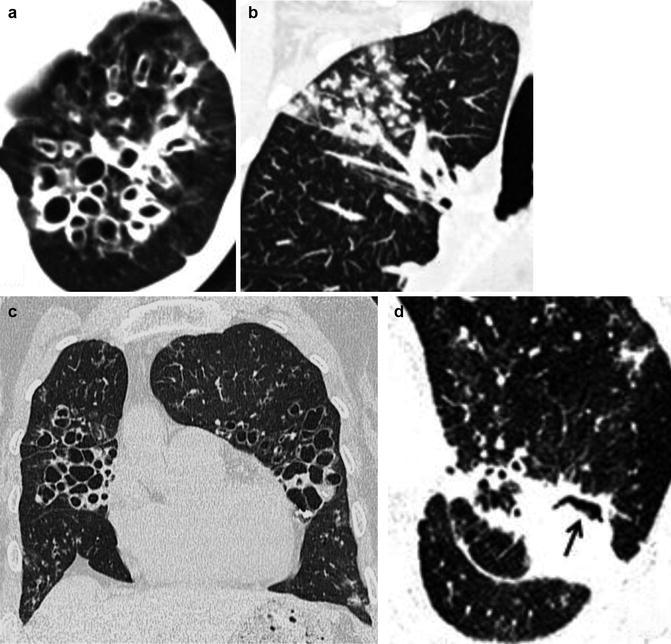

Another ancillary finding is the presence of dilated bronchial arteries in patients with long-standing severe bronchiectasis. This finding is easily identified following administration of intravenous contrast as irregular, tortuous vessels arising from the proximal descending thoracic aorta extending along the central airways toward the pulmonary hila. Identification of hypertrophied bronchial arteries may explain hemoptysis that is otherwise unaccounted for in select acute exacerbation cases (Fig. 18).

Fig. 18.

Massive hemoptysis in a 41-year-old man with common variable immunodeficiency and a history of recurrent infections beginning during childhood. MDCT arterial phase (a, b, d) coronal and (c) oblique sagittal reconstructions reveal bilateral lower lobes bronchiectasis with mosaic attenuation and focal consolidation (likely hemorrhage) and tortuous hypertrophied bronchial arteries (arrows). The patient was treated with repeated bronchial artery embolizations